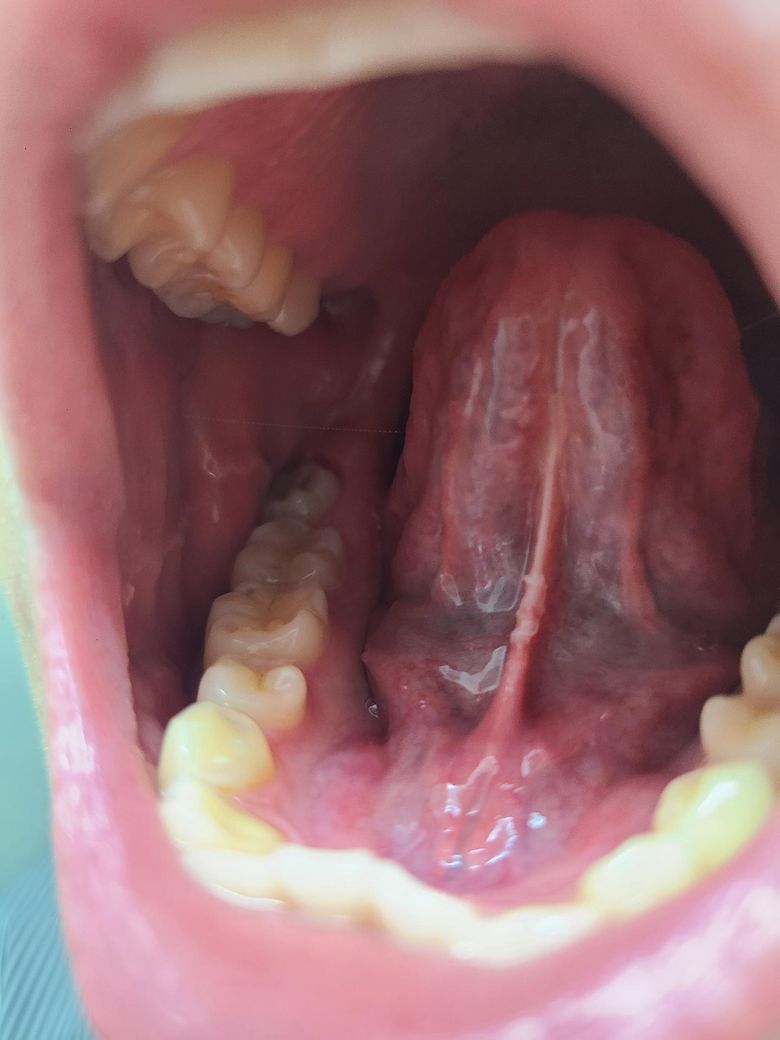

혀 이어지는 부분 물집?......

이게 뭔가요...? 원래 안 그랬는데 까진 느낌 처럼 약간 쓰라려요............................

• 1번 째 사진

혀 안쪽에 생긴 물집은 보통 몸이 피곤하거나 면역력이 떨어졌을 때 나타나는 구내염인 경우가 많아요.

매운 음식처럼 자극적인 것은 피하고 비타민 섭취와 함께 충분한 휴식을 취하며 입안을 청결하게 유지해 보세요.

보통 일주일 정도면 자연스럽게 사라지지만 만약 크기가 커지거나 통증이 심해진다면 꼭 병원에 가보셔야 해요.

가까운 이비인후과나 치과를 방문하여 정확한 상태를 진단받고 그에 맞는 적절한 연고 처방을 받으시길 권해 드려요.